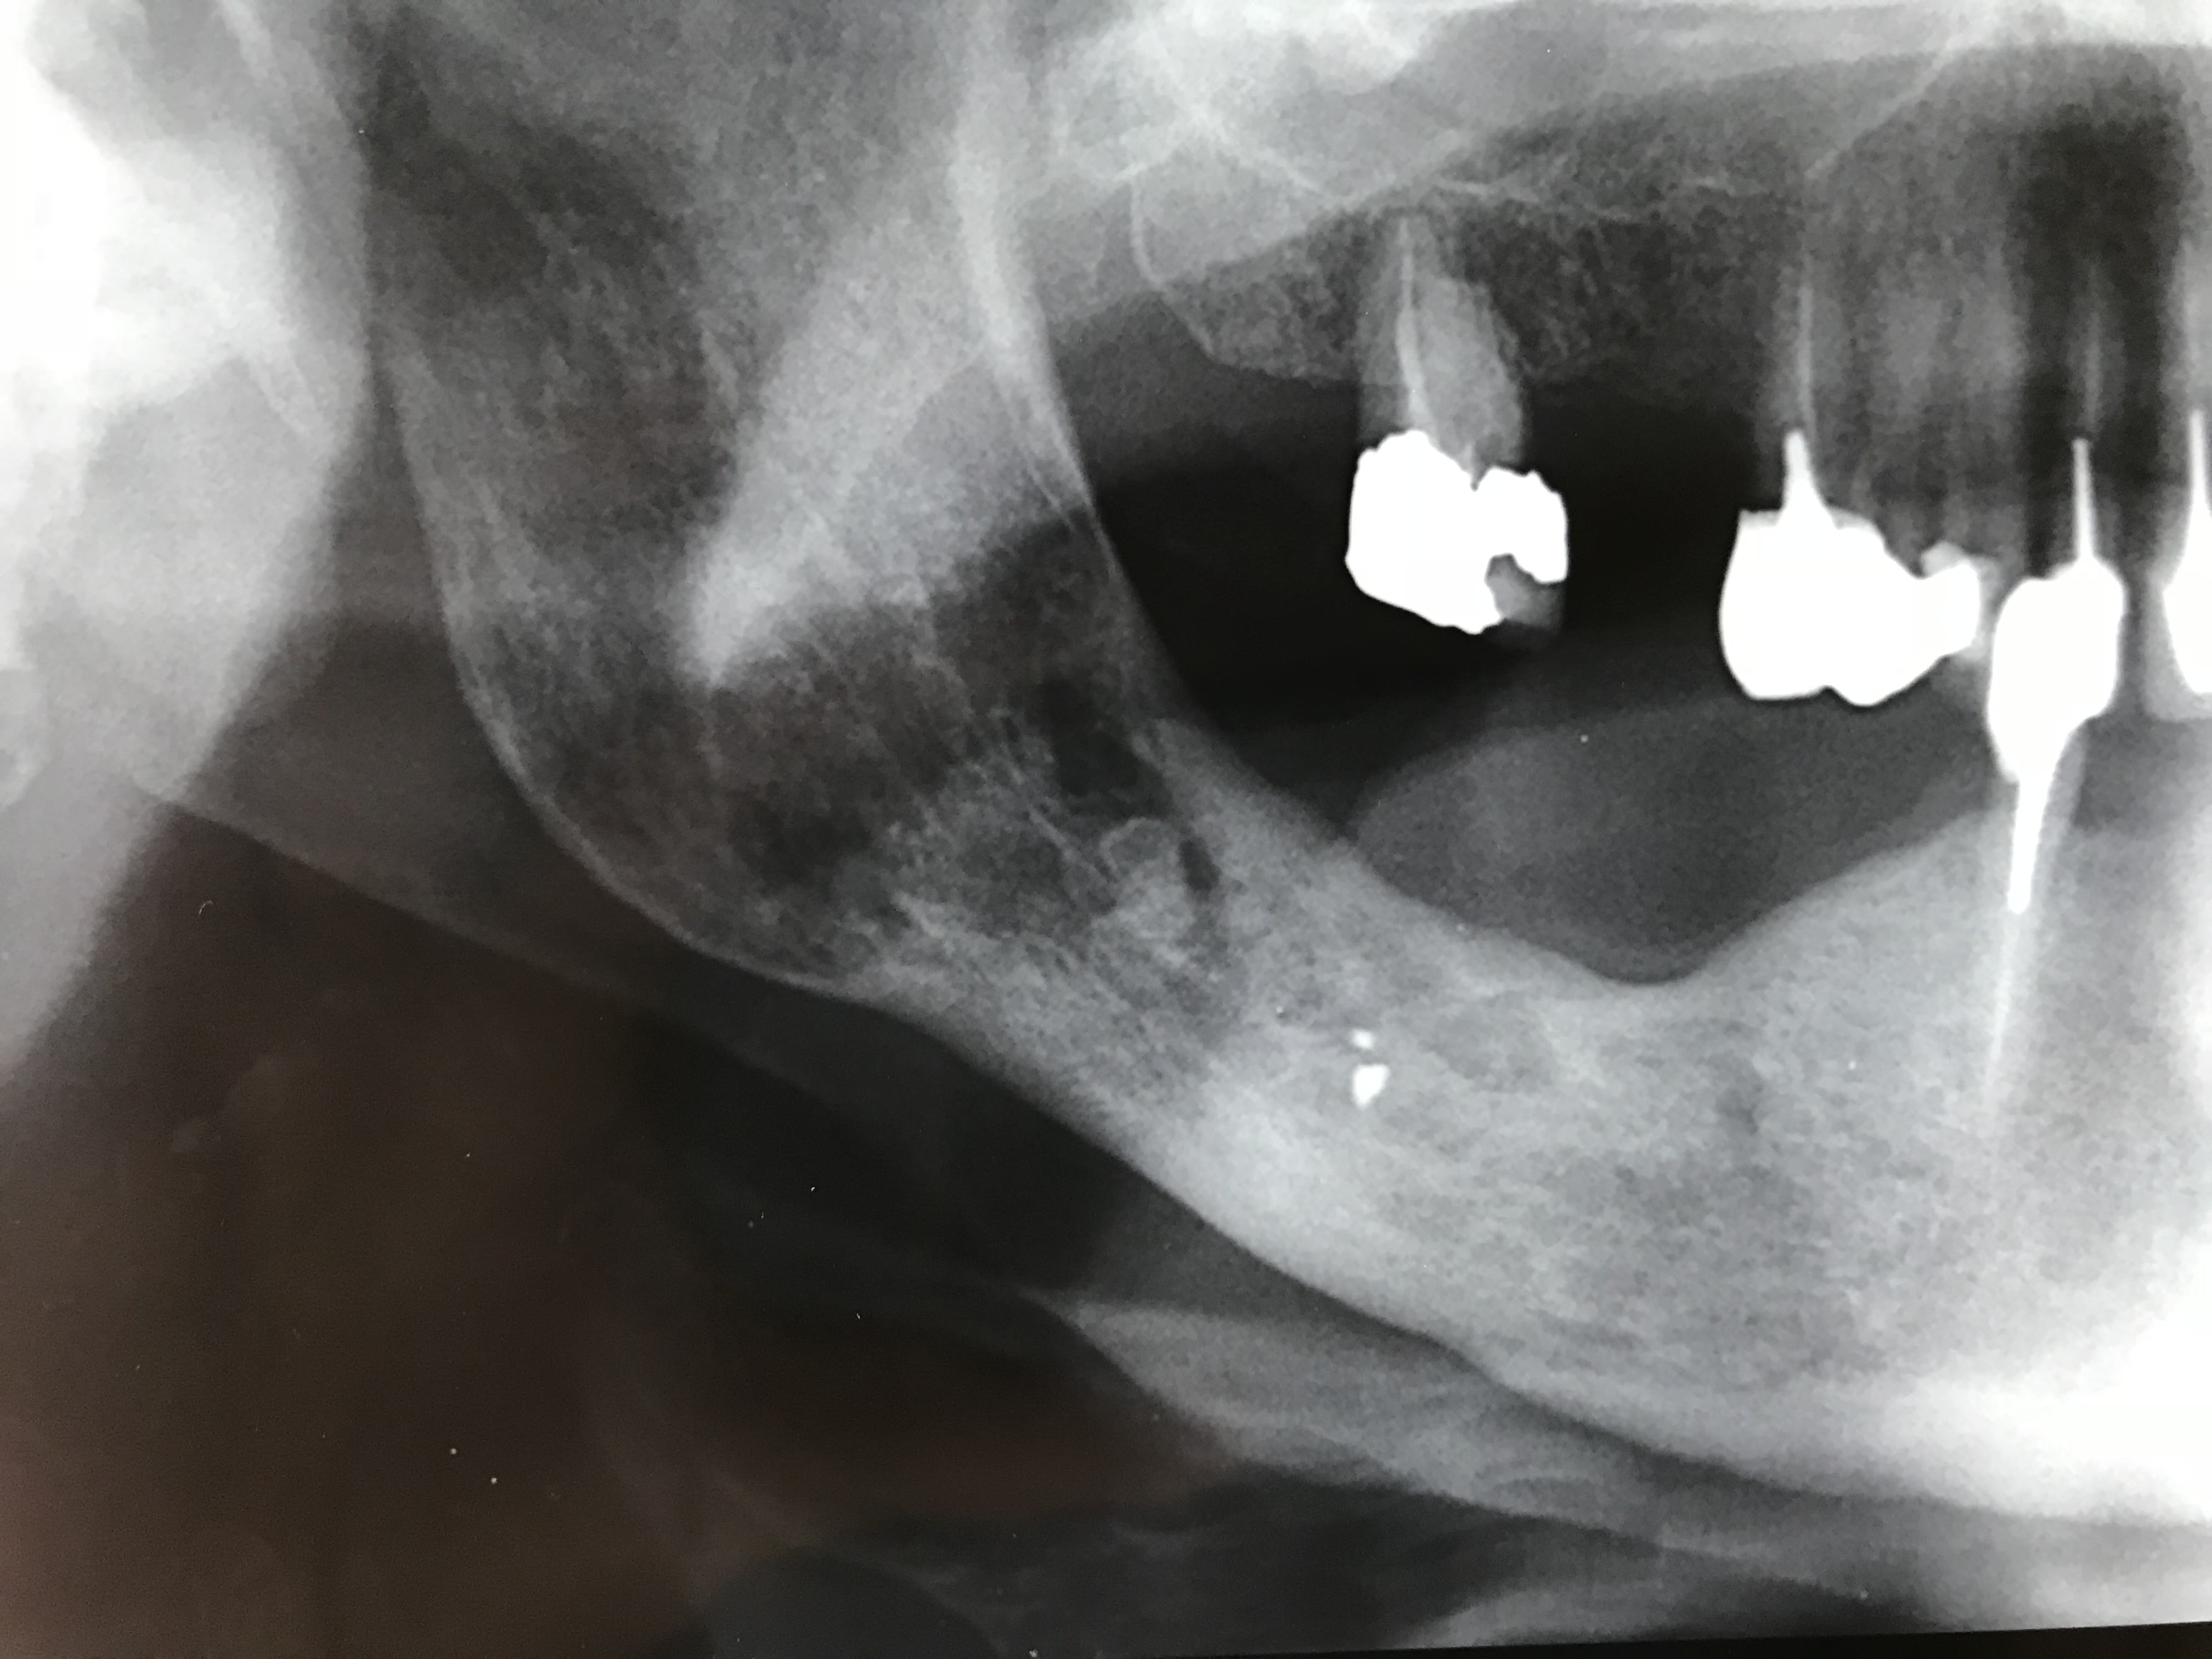

Regardez moi ça : osteoradionécrose de l’angle 10 ans après radiothérapie.

> Regardez moi ça : osteoradionécrose de l’angle 10 ans après radiothérapie.

le patient mange une noisette et crack.